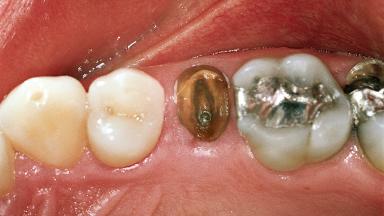

In February 2002, a 31-year-old non-smoking male patient was referred by his dentist after the fracture of the crown of the maxillary right second premolar, tooth 15. The fracture line was located apically to the gingival margin, particularly on the palatal side. Radiographic examination revealed the presence of a previous endodontic treatment with a non-ideal apical seal. There were no signs of periapical osteolysis. The level of the interproximal bone was normal. The patient’s medical history did not reveal any significant findings and he was in good general health.